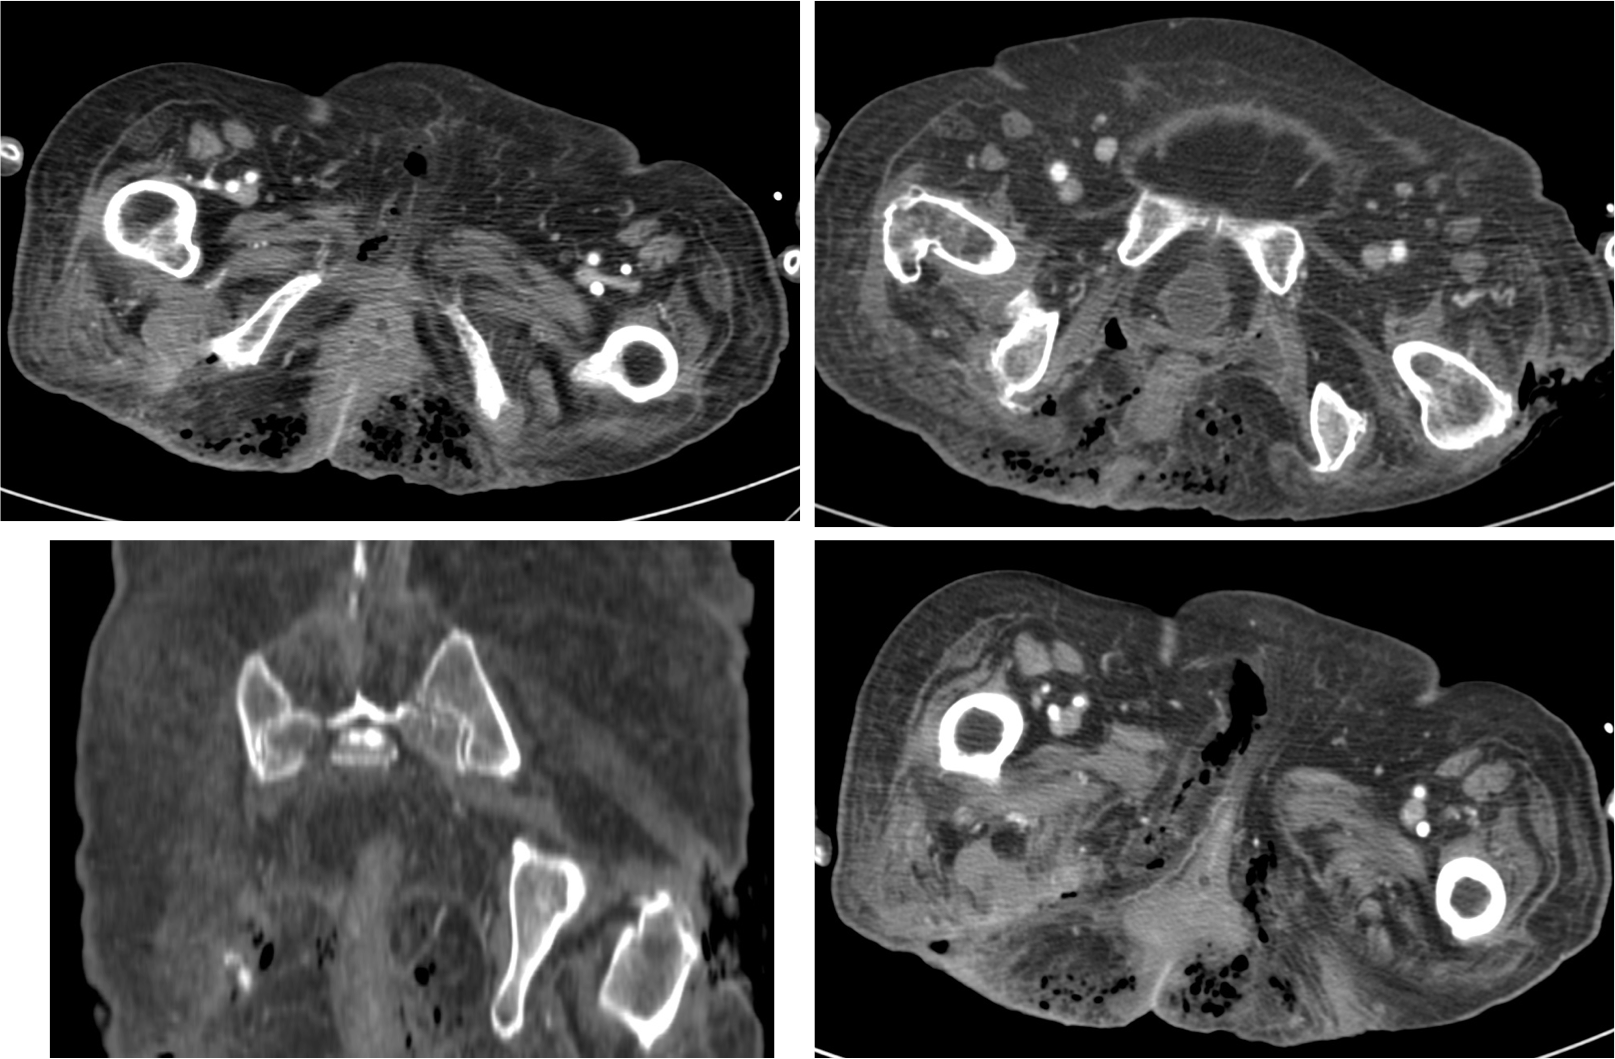

Tomografía Computarizada

Es la técnica que aprota mayor información, por ejemplo nos permite estudiar el retroperitoneo (se han publicado casos de Gangrena de Fournier por perforación de apéndice cecal). Define la causa, muestra el camino por el que se ha extendido el proceso y define las estructuras necrosadas,

- Engrosamiento de fascias e infiltración de partes blandas.

- Presencia de gas.

- Sirve para definir la extensión de proceso previa la cirugía.

- Permite identificar la etiologia del proceso (absceso perianal, fístula, hernias incarceradas, procesos retroperitonales, úlcera de partes blandas…).